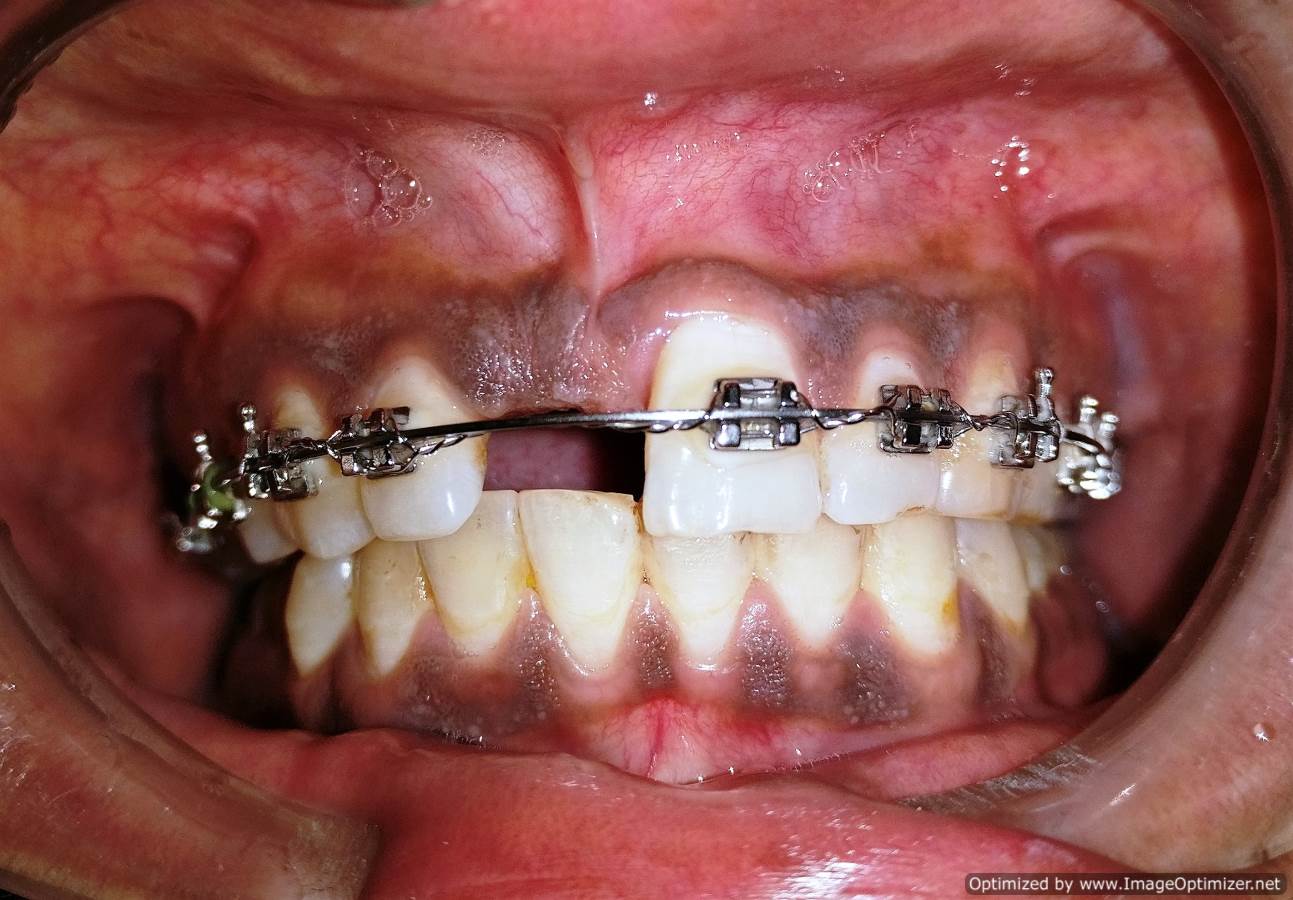

Dental Implant Case Report -03

Home / Case Report / Implant / Dental Implant Case Report -03